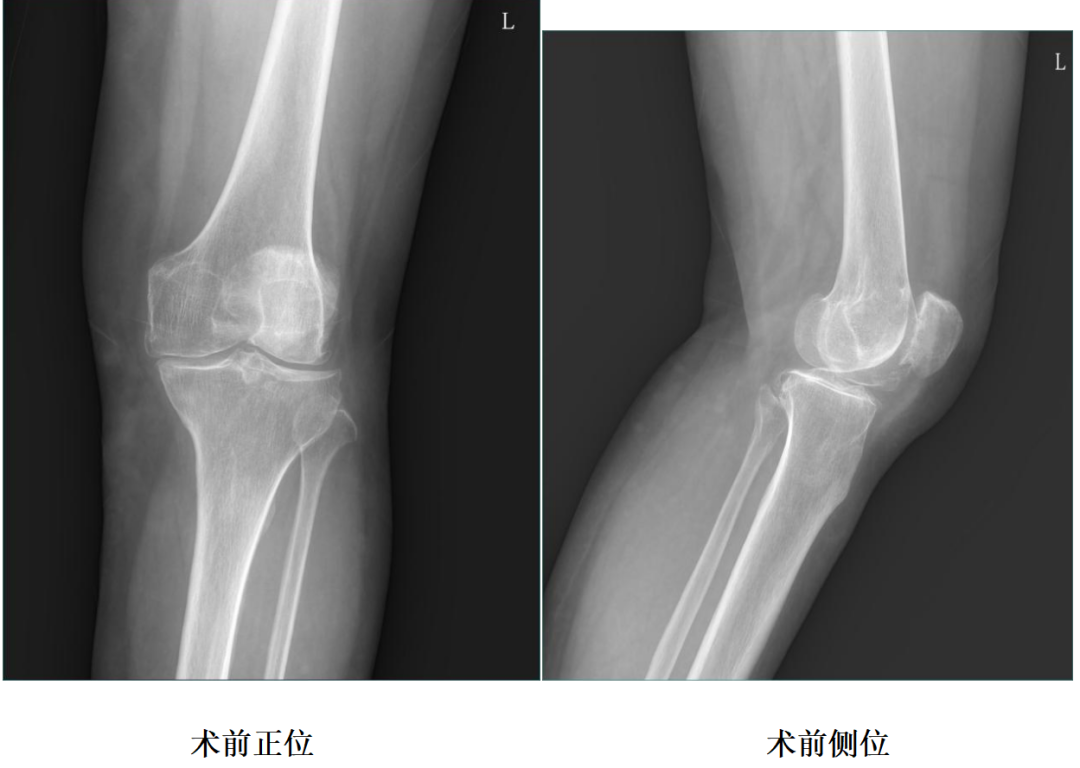

女性患者,66岁,左膝关节疼痛伴活动受限9年余。

体格检查:左膝内翻畸形,约5°,无屈曲畸形。屈曲20°外翻应力下内翻畸形可纠正,屈曲90°可自行纠正。内侧关节间隙处压痛阳性。活动度:0°~115°。

X-Ray:左膝内侧间隙明显狭窄,站立位内侧间隙消失,外侧间隙正常,膝关节稳定。

诊断:左膝关节内侧间室OA。

二、术前X片